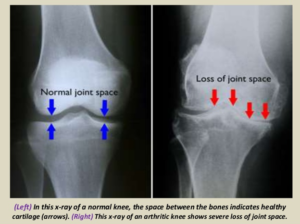

3 key radiographic features of OA?

If all 3 of these findings are not present, another diagnosis should be considered.

X-ray of joint space narrowing